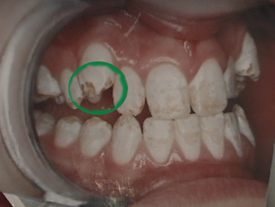

But less about other dangers, for the moment. We want to bring you images of dental fluorosis. They will act as a rough guide to the severity of your condition.

Six types of fluorosis (Source: Fluoride Free, Ireland):

Four pictures of fluorosis (Source: Fluoride: Protected Pollutant or Panacea? Canada):

Five pictures of fluorosis (source: Fluoride Action Network, USA):

Six pictures of fluorosis (source: Provided by Dr Susheela, India):